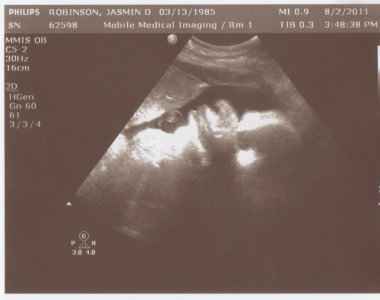

УЗД на 40 тижні вагітності